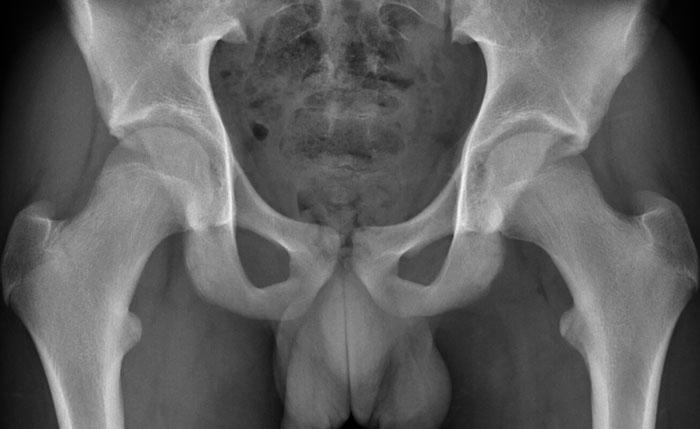

Góc alpha

Góc

alpha được đo bằng cách vẽ một đường tròn qua chỏm xương đùi, một đường thẳng

từ tâm cổ xương đùi đến tâm chỏm xương đùi, và sau đó

một đường thẳng từ tâm chỏm xương đùi đến điểm giao nhau giữa chỗ nối chỏm-cổ xương đùi với đường tròn.

Nếu góc từ 60 độ trở lên, có thể được phân loại là hình thái Cam.

Phép đo này có thể được sử dụng trên cả hình ảnh thông thường lẫn

hình ảnh cắt lớp – trong đó hình ảnh cắt lớp có độ nhạy cao hơn.

Ngưỡng giá trị gần đây đã được tăng lên 60 độ để tăng tính đặc hiệu.

Alpha angle measurement

Hông bình thường có góc alpha nhỏ hơn 60º.

Hông có hình thái Cam có góc alpha lớn hơn 60º.

Tất nhiên, khi hình thái Cam rõ ràng như trong trường hợp này, các

phép đo này là không cần thiết trong thực hành lâm sàng.

Đây là một trường hợp hình thái Cam khá tinh tế ở một nam giới trẻ tuổi.

Lưu ý rằng sụn tăng trưởng mào chậu chưa đóng lại (mũi tên).

Images

Two examples of Cam morphology.